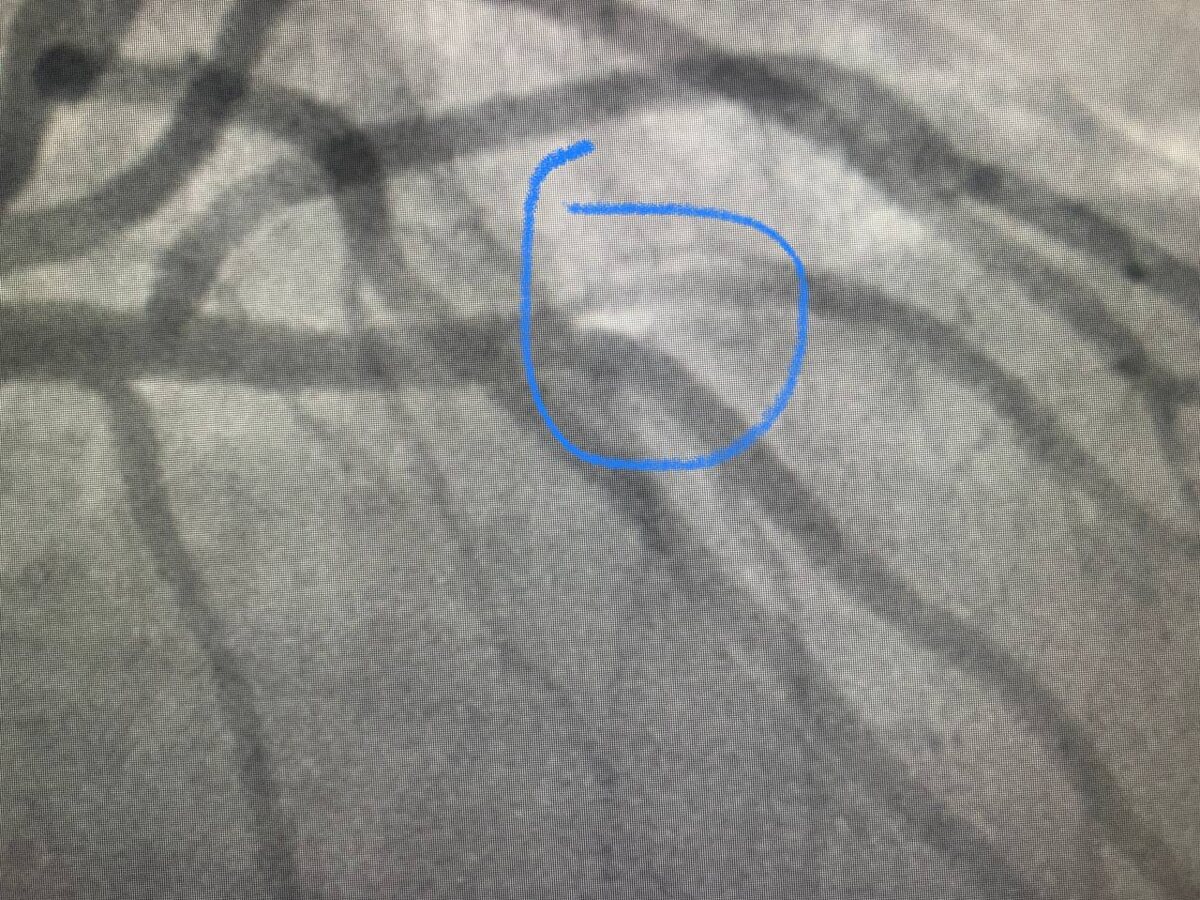

Вот ещё вдогонку, только что сделали ffr, смотрите какой суровый стеноз, 70% точно! Если раньше бы нашли, то пришлось бы делать скорее всего! И не один стент, а два, тк на развилке артерий. А чудесный метод FFR показал, что стенты не нужны. И ситуация у пациента такая, что это большой подарок, тк не нужен будет аспирин с плавиксом. Вот вещь всё-таки